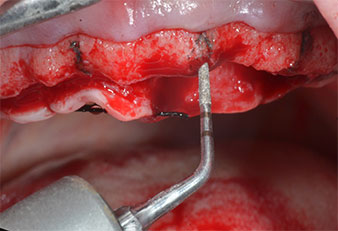

A causa dell'osso relativamente duro (D2) in quest'area, le sedi dell'impianto di 10 mm nelle posizioni 11 e 21 sono state finalizzate con un trapano rotante da 4 mm di diametro, in combinazione con un contrangolo chirurgico W&H WS-75 L, il motore per impianto W&H Implantmed e il modulo opzionale Osstell ISQ di W&H. Al contrario, a causa dell'osso morbido, le sedi posteriori sono state preparate a un diametro finale di 3 mm utilizzando lo strumento Piezomed I3P. Gli impianti sono stati infine posti per via transgengivale sull'osteointegrato per tre mesi (Figg. 6-10). La protesi dentaria esistente è stata mantenuta su quattro impianti provvisori (Fig. 8).